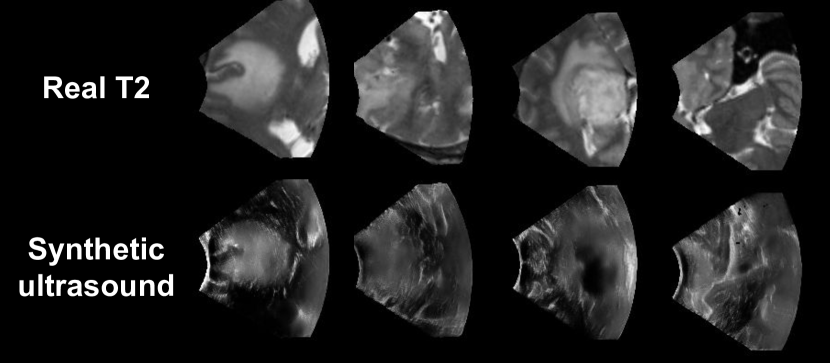

Refer to caption

Figure 4: Example of synthetic ultrasound images generated from T2 scans of the BraTS dataset.

The current framework enables the generation of iUS data using T2 MRI data. Since image delineation is much more efficient on MRI than on US, annotations performed on MRI could be used to train a segmentation network on pseudo-iUS data, as performed by the top-performing teams in the crossMoDA challenge [9]. For example, synthetic ultrasound images could be generated from the BraTS dataset [1], the largest collection of annotated brain tumor MR scans. Qualitative results shown in Appendix demonstrate the ability of our approach to generalize well to T2 imaging from BraTS. Finally, the synthetic images could be used for improved iUS and T2 image registration.